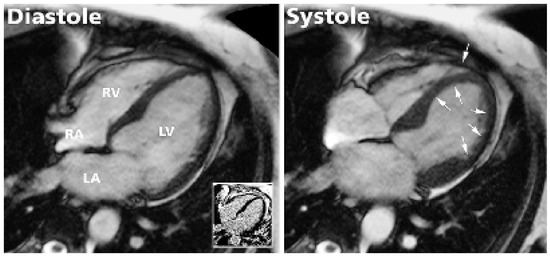

While substantial progress has been made over the past decade in the medical treatment of heart failure, certain patients fail to respond to optimal treatment despite the availability of excellent drugs. Cardiac resynchronisation therapy, or multisit...